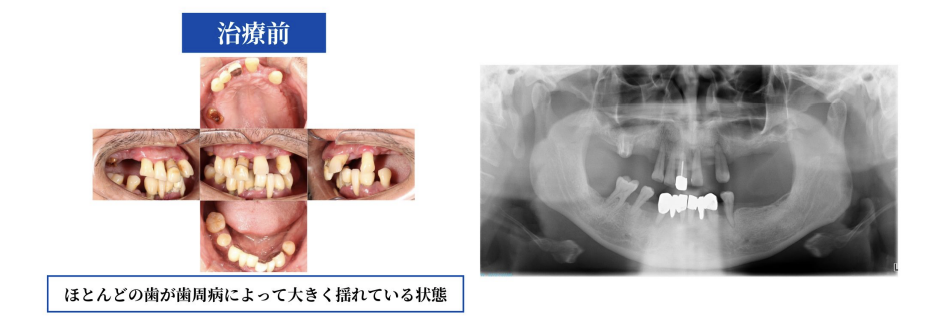

「歯がボロボロで、噛むのがつらい」患者様が来院されたとき、ほとんどの歯が歯周病によって大きく揺れている状態でした。

検査の結果、残念ながら歯を残すことは難しい状態でした。長年使ってきた歯をすべて抜く決断は、簡単なものではありません。